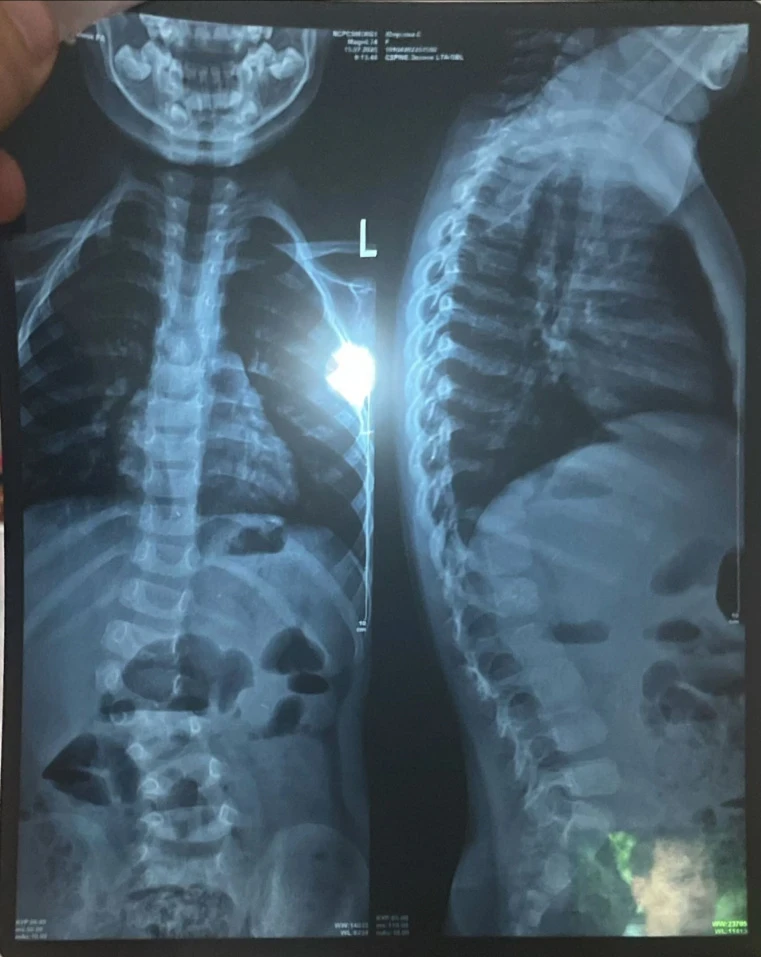

"Понимая, что лечение не помогает, мы обратились к специалистам из Турции. Они уверены, что единственным вариантом является операция, и чем быстрее она будет проведена, тем лучше для развития Сумаи. Недавно мы также узнали, что у нее есть лишняя кость на позвонке, что видно на рентгене, и это также связано с сколиозом", - рассказывает мама.

Из-за искривления позвоночника у Сумаи уже наблюдается асимметрия тела: одно плечо ниже другого, а одна нога короче.